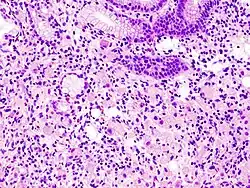

En histología, una célula en anillo de sello es aquella célula con una vacuola grande. El tipo maligno se observa predominantemente en carcinomas.

El nombre de la célula proviene su aspecto; las células en anillo de sello aparentan ser anillos de sello . Contienen una gran cantidad de mucina, la cual empuja al núcleo hacia la periferia de célula. El contenido de mucina en las células en anillo de sello imita la apariencia de un agujero para el dedo y el núcleo imita aspecto de la cara del anillo en perfil.

Un número significativo de células en anillo de sello, generalmente, se asocia con un pronóstico peor.[7][8]